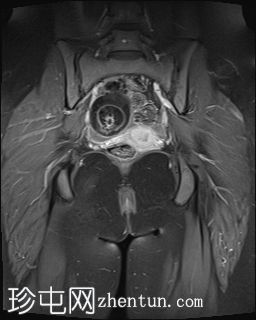

4.jpeg

冠状扫描T1

脂肪密度

右侧附件区可见较大囊性肿块,内含脂肪和液体,大小约为86毫米 x 60毫米。右侧血管蒂扭转,呈漩涡征。右侧卵巢可见增大充血的卵泡,为囊性肿块病变。左侧卵巢正常。